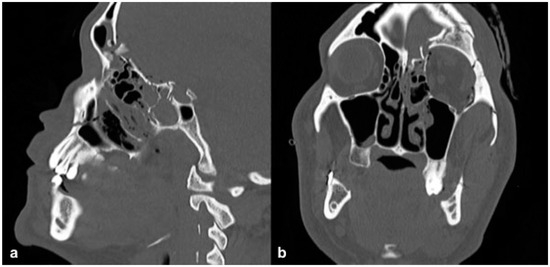

The frontal sinus outflow tract (FSOT) is an hourglass shape, made up of the infundibulum superiorly, the frontal recess inferiorly, and separated by the ostium or narrowest portion (3–4 mm). There are a variety of pneumatization patterns of ethmoidal cells that are adjacent to the FSOT.[13] The FSOT is found in the posterior, inferior, and medial portion of the frontal sinus. (Figure 1).

Figure 1. (a) CT in the sagittal plane of the frontal sinus outflow tract (FSOT). (b) Corresponding illustration of the frontal sinus outflow tract (dotted arrow) bordered anteriorly by the agger nasi cell and posteriorly by the suprabullar and bullar cells.